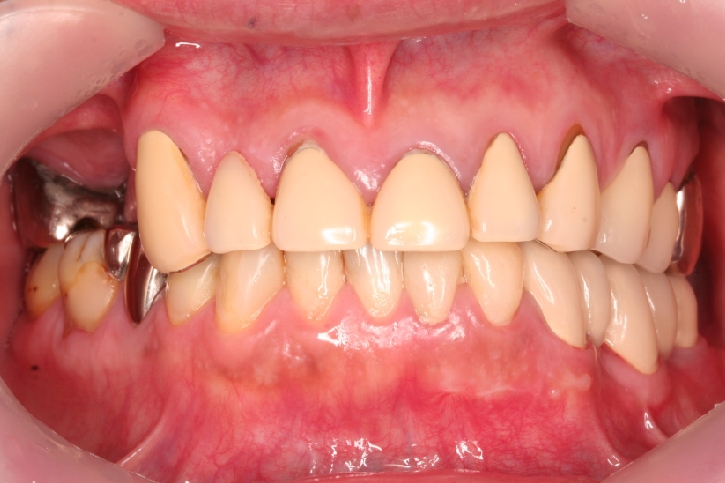

オールセラミックス修復

担当歯科医師:丸林浩太郎

2013年5月11日千葉市中央区 K.N様 上顎12番 オールセラミッククラウン修復